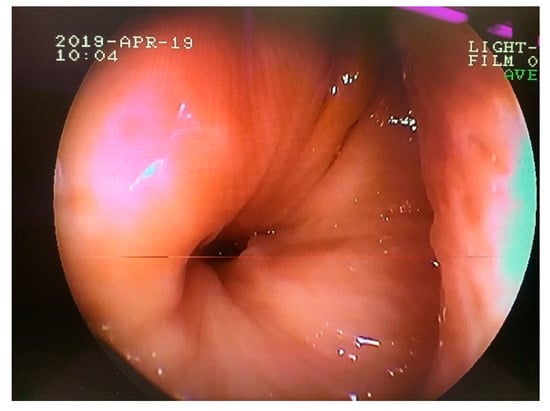

The apical part of the plug was remodeled and adjusted to the alveolus. The plug was frequently loosened, necessitating its replacement and resulting in the contamination of the nasal cavity with feed. In the 12th week of treatment, the plug was modified by adding a small plastic sleeve into the PVS packing material, to which a nylon thread was attached. Free ends were fastened to a button fixed on the surface of the maxillary bone (Figure 8). Additional injections of the fistula with platelet-rich plasma (PRP) were conducted in a once-weekly regimen for 3 weeks. Endoscopic examination performed in the 16th week of treatment revealed a markedly reduced tract of the fistula to a 1 mm diameter (Figure 9). Two months later, an autologous cancellous bone graft was taken from tuber coxae to promote bony fusion and revascularization. First, the oronasal fistula was filled with graft and the alveolar cavity was then covered with a modified polyvinyl siloxane plug, as previously described, for 4 weeks. Seven months after the initial extraction, endoscopic examination revealed the complete closure of the fistula.

Figure 9.

Transnasal endoscopic examination obtained 16 weeks after the initial surgery. Note the nasal opening of the persisted oronasal fistula at the level of 208 alveolus.